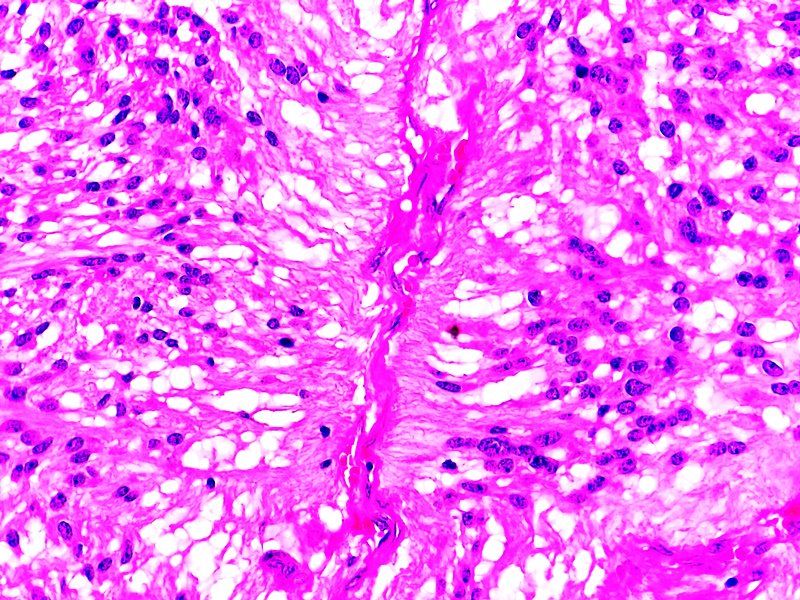

Próstata. Tumor estromal de potencial maligno incierto. Tinción HE.